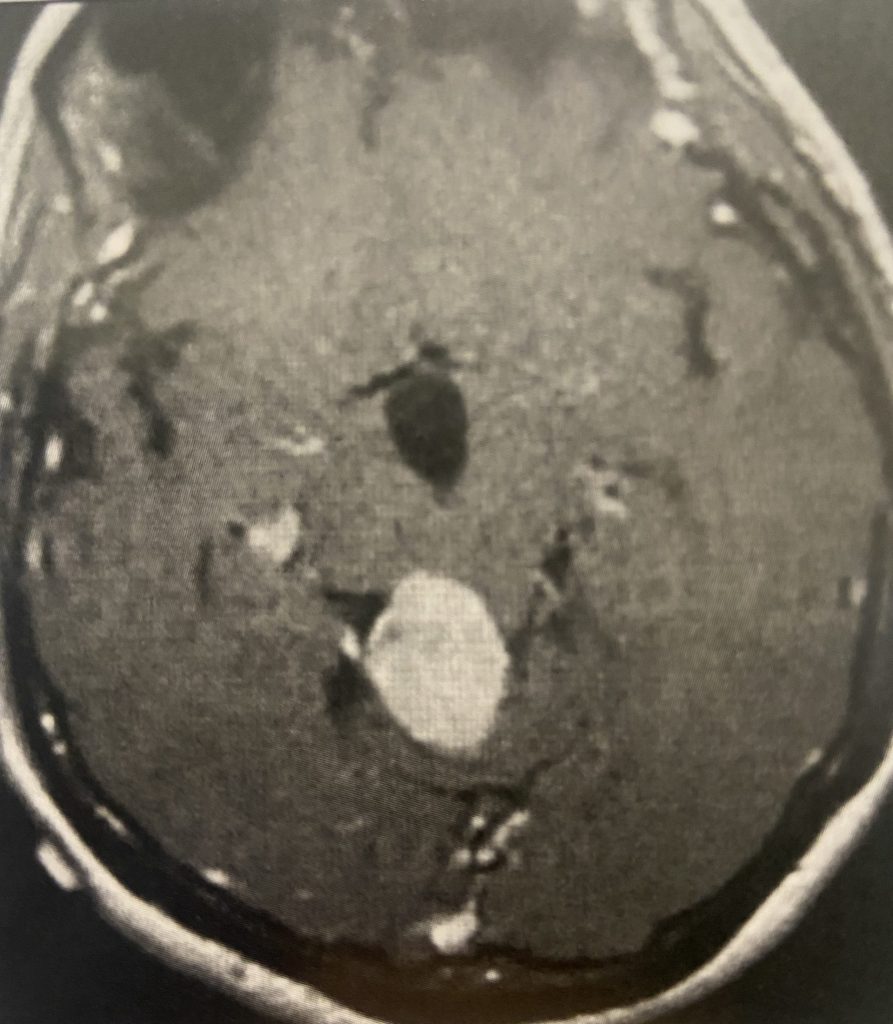

Figure 2: Images demonstrating the right occipital / transtentorial operative approach.

The traditional surgical approach to this region is the midline supracerebellar approach, performed with the patient in the seated position. We chose instead the right occipital / transtentorial approach. The major advantages of this alternative approach are (1) it is much easier technically for the surgeon, and (2) the risk of a serious air embolus is much lower. The major risk of surgery in the pineal region is injury to one of the large deep veins, which can result in a serious venous infarct.